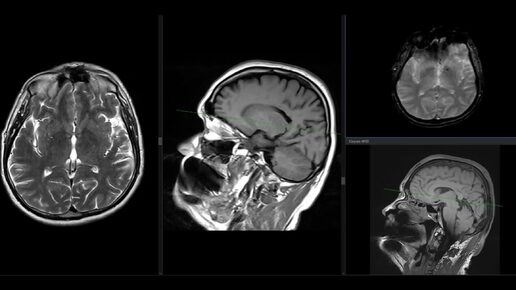

МРТ головного мозга